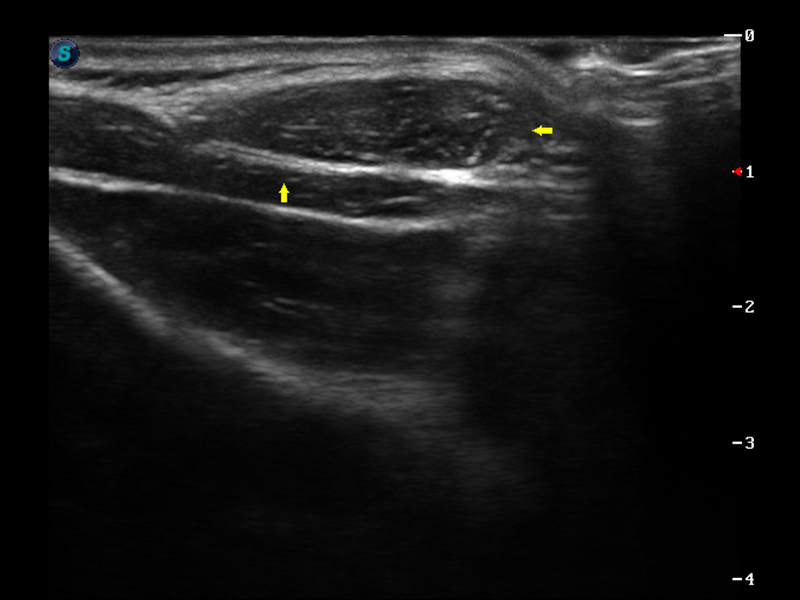

S9便携式彩色多普勒超声诊断仪是米兰官方网站研发的高端便携彩超设备,外观设计新颖、产品性能卓越。S9在便携超声领域采用了突破传统的触摸屏交互设计,并以先进的软件硬件技术和设计理念,为您带来清晰的图像质量、稳定的工作性能和便捷的操作体验。